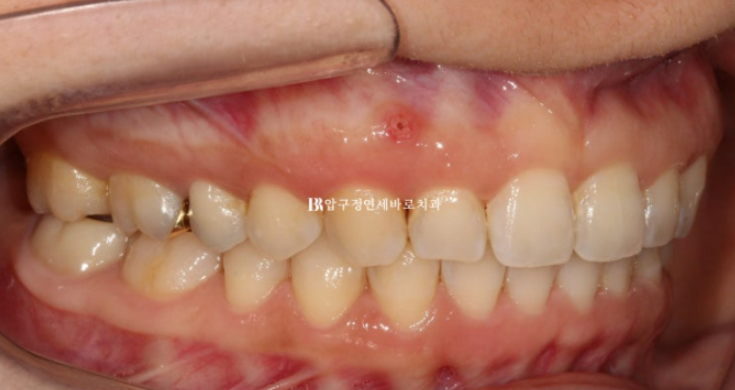

예전 교정치료의 흔적으로 위 앞니에는 철사유지장치가 붙어있습니다.

철사 유지장치가 여러 조각이 나있는 이유는?

과개교합 때문입니다.

과개교합이 남은 채로 교정치료가 마무리가 되면 철사유지장치가 아랫니와 닿아 불편하고 자꾸 떨어지고 문제가 생깁니다.

과개교합은 이렇게 교정 완료 후 재발 가능성과 유지관리에 큰 장애가 됩니다.

반드시 해결하는 것이 좋습니다.

파란 화살표는 임플란트 입니다.

임플란트가 있는 쪽 어금니는 임플란트 치아를 표함하여 이동이 제한이 됩니다.

따라서 임플란트가 있는 쪽 교합을 맞추는 데 한계가 있습니다.